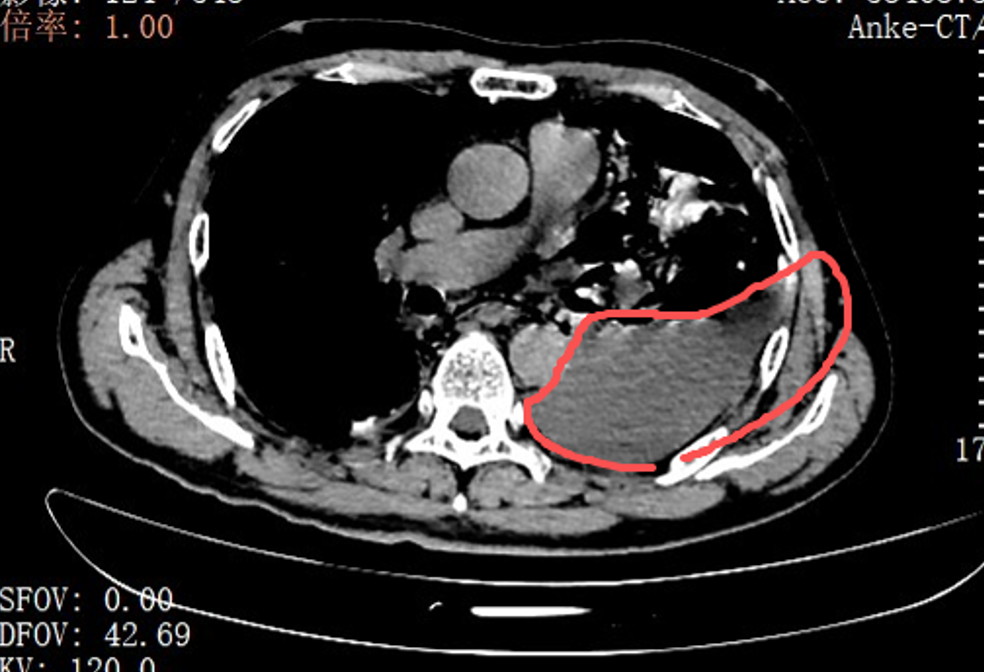

红圈区域是食品残渣、消化液破入食管